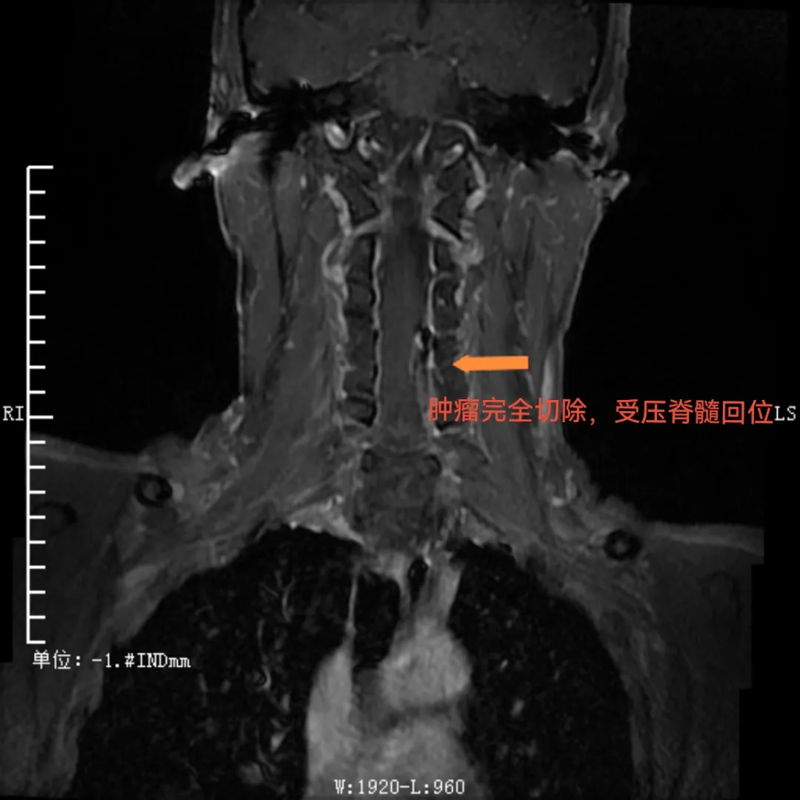

手术过程中,先由脊柱外科团队采取“单开门”的方式打开经4、5节段左侧椎板并向右侧掀起。这种独特的操作方式能够充分暴露肿瘤区域,再由神经外科团队在显微镜下打开硬脊膜并完整切除肿瘤。手术顺利,如今患者已出院,本人及家属对手术效果相当满意,赠送锦旗表示感谢。

术后,肿瘤完全切除,受压脊髓回位

与传统手术需要完全切除肿瘤节段全椎板不同,这种新的手术方式术后仅需将掀起的椎板纳还并以丝线固定即可,无需使用金属连接耗材固定。这不仅使得复位效果更佳,而且患者在术后复查CT、磁共振时无金属伪影干扰,让检查结果诊断更准确,还为患者节省了相当大的一笔费用。